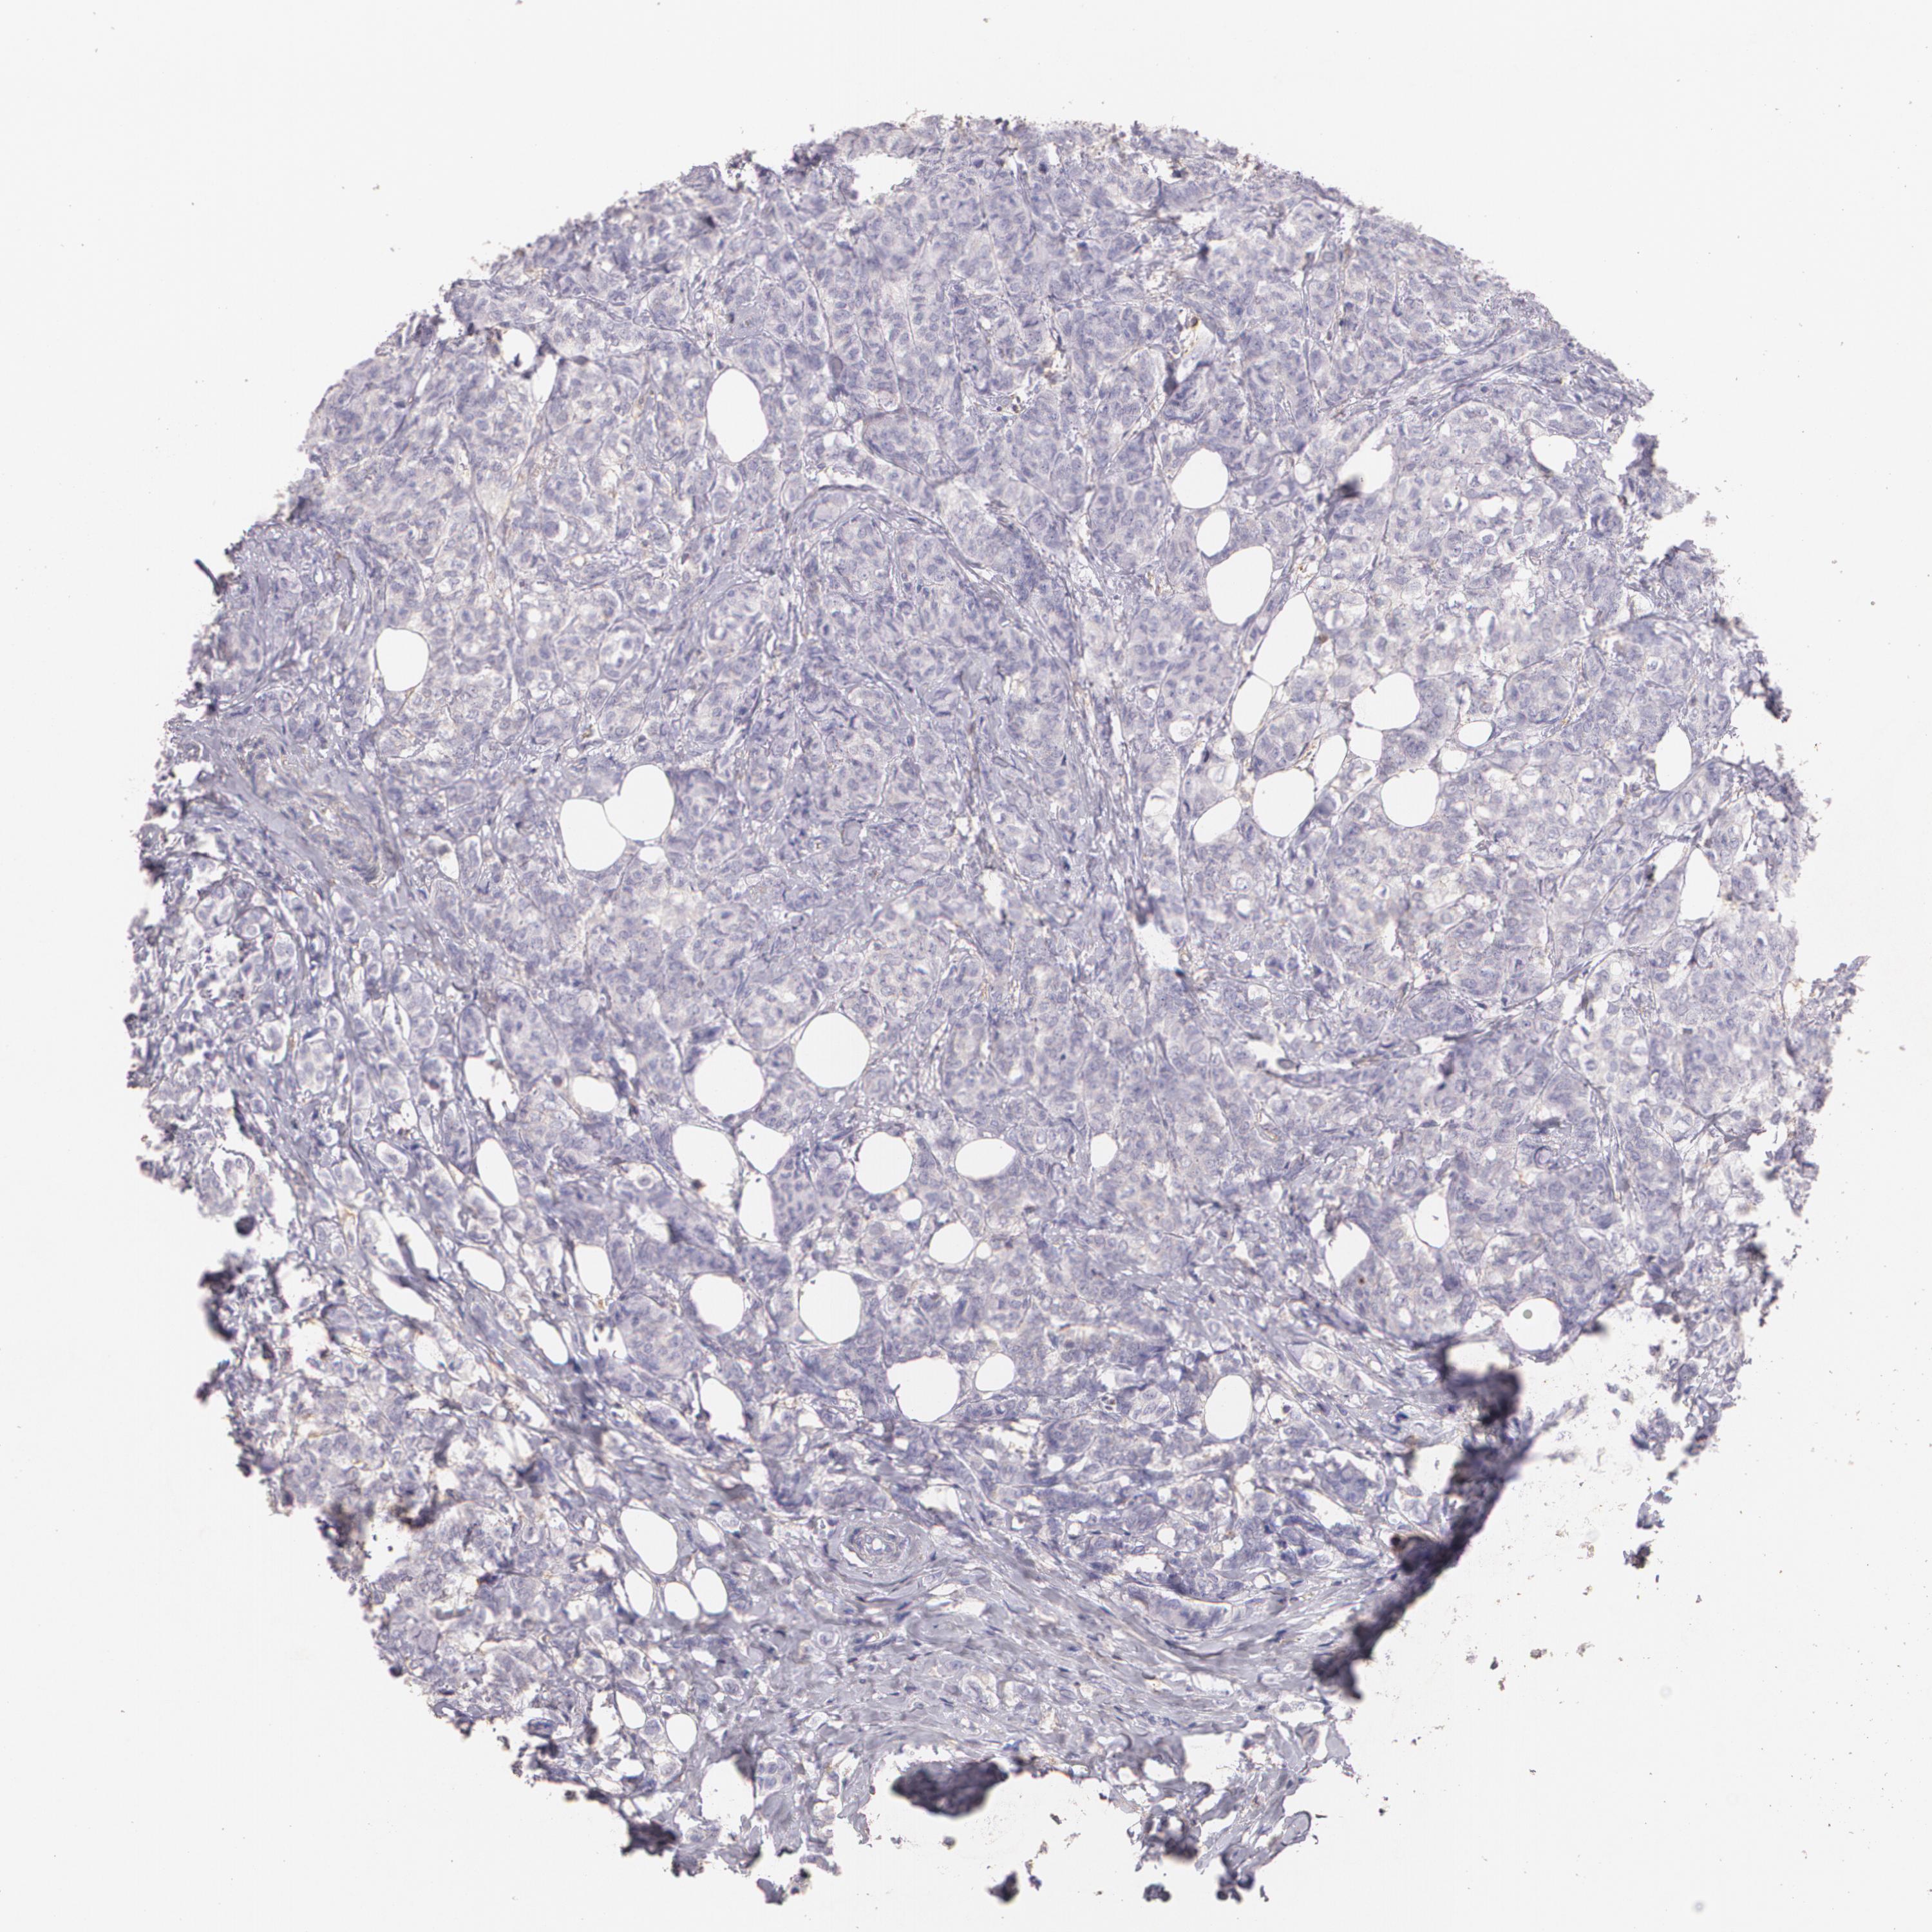

BRCA TCGA BRCA VALIDATION PROTEIN EXPRESSION

Breast cancer

Human cancer

Breast invasive carcinoma